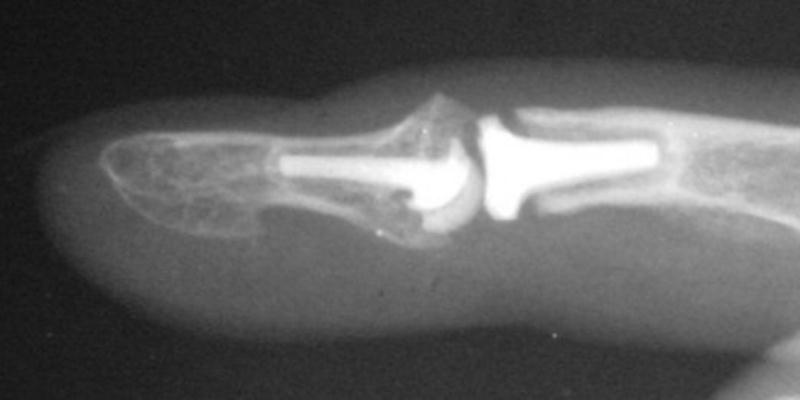

The final implant:

Xrays one year out.